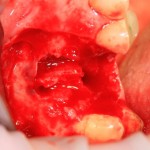

Немедленная имплантация — оптимальное решение в любой клинической ситуации